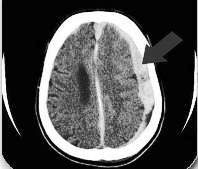

CT snimak mozga

Slika: CT snimak mozga – strelica pokazuje subduralni hematom

(ugrušak ispod tvrde ovojnice mozga – dura mater)

Treba imati u vidu da je izmedju 2 i 6 nedelje hematom izodenzan sa susednim mozdanim tkivom i pokazuje samo pomeranje bočne komore. U kasnijoj fazi hematom je hipodenzan na CT snimku. NMR je koristan kod subakutnih hematoma.